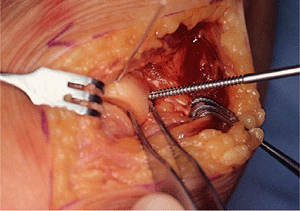

![]() |

|

Figure 5-6. The lateral capsule is opened just anterior to the lateral complex, which originates at the humerus and attaches to the ulna (A). The fracture has been identified and the hematoma cleaned with a water pick (B).

Figure 5-7. A,B:

The fracture has been reduced. A K-wire is used to secure the fracture and it is placed in the anterior half of the fracture fragment. |